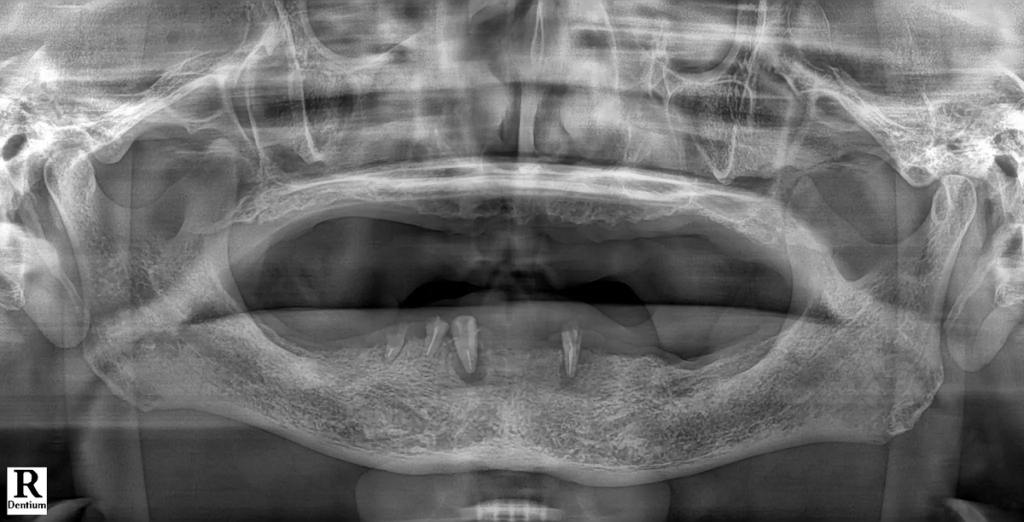

디지털 풀아치 임플란트는 한 턱에 4~6개의 임플란트로 전체 치아 기능을 회복하는 치료입니다. 먼저 3D CT, 파노라마, 디지털 구강 스캐너를 통해 잇몸뼈의 두께·밀도·신경 위치를 3차원으로 분석합니다. 이 단계에서 임플란트가 가능한 뼈 영역과 피해야 할 위험 구간을 명확히 구분합니다.